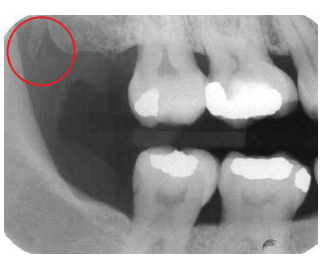

A estrutura que aparece atrás do túber da maxila, destacada na imagem abaixo, denomina-se:

Processo coronóide.

Processo estiloide.

Corpo da mandíbula.

Hâmulo pterigoideo.